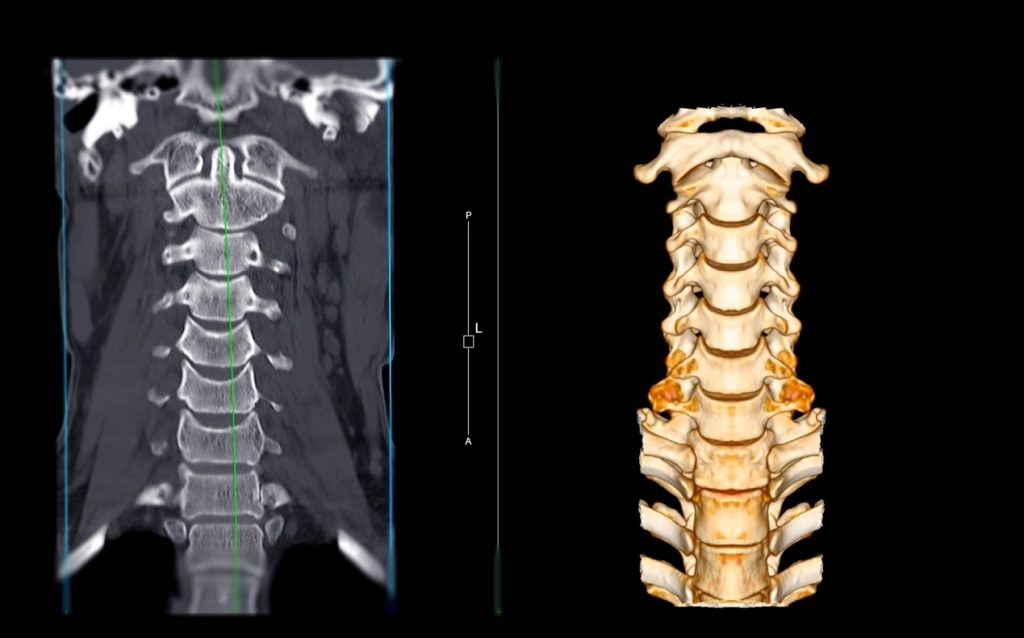

Η αξονική τομογραφία (CT) είναι ένα εργαλείο απεικόνισης που συνδυάζει τις ακτίνες Χ με την τεχνολογία υπολογιστών για να παράγει μια πιο λεπτομερή, εγκάρσια εικόνα του σώματός σας. Μια αξονική τομογραφία επιτρέπει στον γιατρό σας να δει το μέγεθος, το σχήμα και τη θέση δομών που βρίσκονται βαθιά μέσα στο σώμα σας, όπως όργανα, ιστοί, οστικές δομές ή όγκοι.

Τι συμβαίνει κατά τη διάρκεια μιας αξονικής τομογραφίας

Κατά τη διάρκεια της σάρωσης, ξαπλώνετε όσο το δυνατόν πιο ακίνητοι σε ένα τραπέζι που ολισθαίνει στο κέντρο του κυλινδρικού αξονικού τομογράφου. Η διαδικασία είναι ανώδυνη. Ένας σωλήνας ακτίνων Χ περιστρέφεται αργά γύρω σας, λαμβάνοντας πολλές εικόνες από όλες τις κατευθύνσεις. Ένας υπολογιστής συνδυάζει τις εικόνες για να παράγει μια καθαρή, δισδιάστατη εικόνα σε μια οθόνη τηλεόρασης.